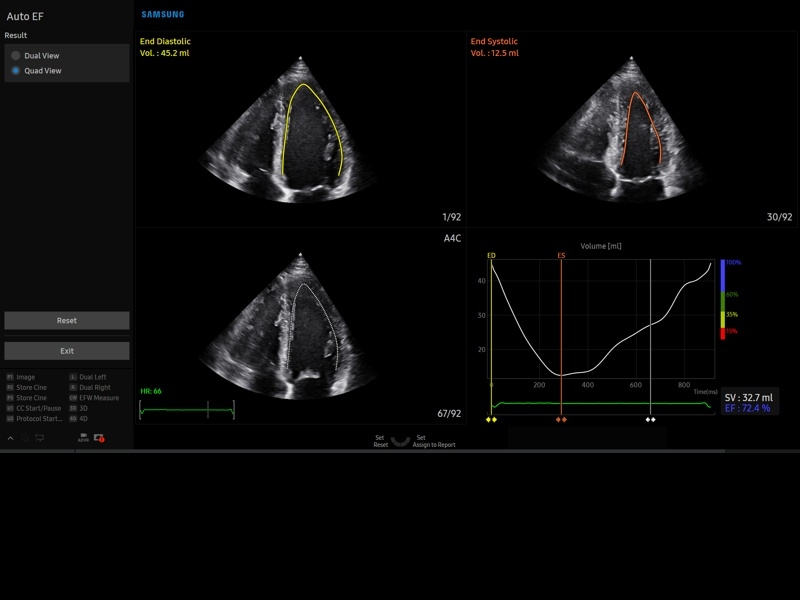

Ультразвуковой сканер V8-RUS является экспертным классом (премиальный уровень) и производится компанией Samsung Medison. Сканер V8 обеспечивает превосходное качество изображения благодаря использованию технологии Crystal Architecture™, которая включает в себя передовое аппаратное обеспечение, монокристальную технологию изготовления датчиков и сложную программную обработку ультразвуковых лучей.

Samsung Medison V8 представляет собой современную ультразвуковую систему, в которой воплощен многолетний опыт компании Samsung в создании эргономичного и интеллектуального диагностического оборудования. Система оснащена передовыми инструментами автоматизации, которые значительно упрощают рабочий процесс и повышают эффективность исследований.

• Кардиологический пакет с функцией StressEcho

• Кардиопакет: тканевый допплер (TDI) + анатомический М-режим + цветной М-режим (CM) + программное обеспечение.

• МодульStrain+- программа не векторной оценки степени сократимости миокарда с выведением автоматически расчетов и графиков на экране отдельно по каждому сегменту.

• Пакет кардиологических исследований.

М-режим:измерение диаметра аорты, передне-заднего размера ЛП, толщины МЖП (систолическая и диастолическая), толщины ЗСЛЖ (систолическая и диастолическая), размеров ЛЖ и ПЖ (систолический и диастолический), ФВ (Teichholz).

B-режим:измерение диаметра аорты (восходящей, дуги, нисходящей, на уровне синусов Вальсальвы, на уровне створок аортального клапана), определение размеров ЛП и ПП (максимальный, минимальный, систолический, диастолический, переднее-задний, верхнее-нижний, медиально-латеральный), расчет объемов ЛП и ПП, объемов ЛЖ (метод "Площадь-Длина", метод дисков (Simpson)), массы миокарда ЛЖ, индекса массы миокарда ЛЖ.